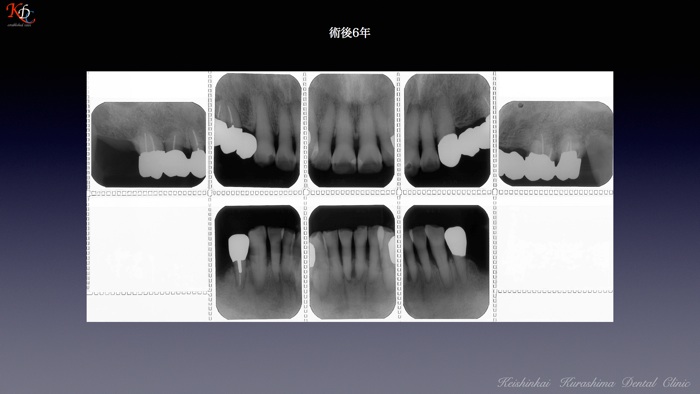

治 療例 1